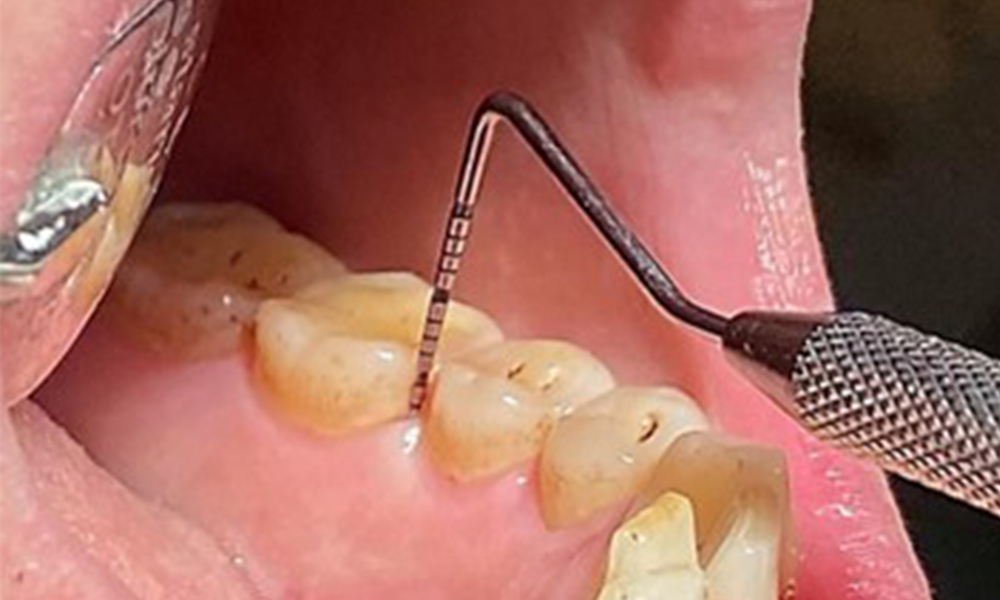

Due to the otherwise favourable general medical condition, the needs determined during the intraoral examination will be decisive for their treatment. It will be essential to periodically determine the probing depths. Gingival bleeding decreases in smokers, which is why the clinical diagnosis of periodontitis can only be made by probing (Fig. 7). Placing exclusive focus on the determination of bleeding indices may obscure existing periodontitis or gingivitis. (5)

Instruction and motivation are important components of these appointments. Good home-based intraoral hygiene behaviour and understanding are important for patients. Plaque accumulation is particularly evident in the cervical regions (Fig. 8).